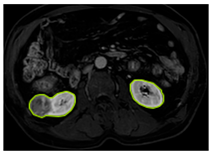

3.2.1. ROI Dataset

The images used in the study include different anatomical areas, such as the liver, spleen, and intestine. However, in order to process the data more quickly and provide more accurate results from the analysis, only the kidney areas (Regions of Interest, ROI) were extracted and evaluated. The Roboflow platform was used for spatial matching and segmentation of the kidneys. Polygonal ROI regions were defined by applying the semantic segmentation method, and then the transformations performed were verified by the radiologist, increasing the reliability of the system. In our study, MRI phase images were acquired at a resolution of 512 × 512 and the renal region of interest (ROI) was segmented and resized to 224 × 224 for input into the DenseNet architecture. In a similar study, Alhussaini et al. utilized 512 × 512 CT images and processed tumor-containing ROIs for their analysis; however, segmented region details were not provided [23]. Another study aimed to differentiate ccRCC from oncocytoma by extracting ROIs from T2-weighted images (T2-WI), pre-contrast T1-weighted images (T1-WI), and post-contrast arterial and venous phases. Tumor regions segmented at 100 × 100 mm were subsequently resized for input into the AlexNet model [24]. Unlike these studies, our approach involves segmenting the entire kidney, rather than solely the tumor region, to enable the deep learning model to leverage structural information for the organ as a whole.

Table 2 shows sample images containing ROI areas for different phases.

Table 2.

ROI areas in different phases.